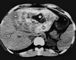

Диагноз ставят на основании эпидемиологического анамнеза (пребывание больного в эндемическом по альвеолярном эхинококкозе очаге), характерных клинических симптомов и специальных тестов — эозинофилии, увеличения СОЭ, диспротеинемии, положительной внутрикожной пробы Касони (при повторной постановке возможен анафилактический шок!), реакции латекс-агглютинации. При обзорной рентгенографии области печени в зоне паразитарного узла выявляются обызвествления в виде «известковых брызг» (рис. 2). Наиболее точные диагностические и топографические данные получают при ультразвуковом исследовании (рис. 3) и компьютерной рентгеновской томографии печени (рис. 4). Реже для уточнения характера, локализации и величины паразитарных узлов печени используют ее сканирование, лапароскопию, ангиогепатографию (рис. 5), пункционную биопсию. А. печени необходимо дифференцировать с циррозом печени, раком и эхинококкозом печени.